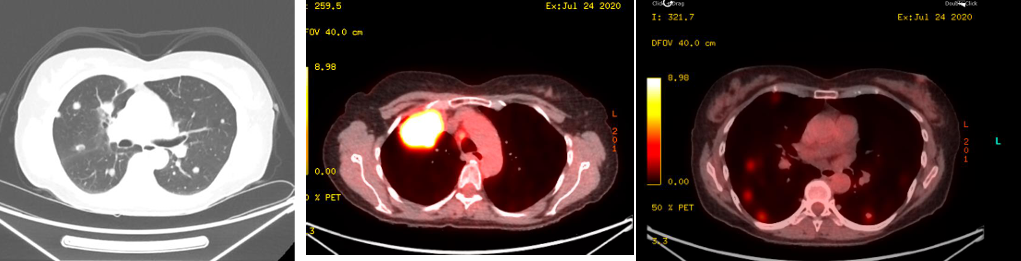

胸部CT显示,右肺上叶巨大肿块(6.5cm),伴双侧多发肺结节及纵隔淋巴结肿大。脑MRI未见转移。

临床诊断:肺腺癌,cT3N2M1b(IVB期)。

分子特征:KRAS G12C突变,伴随STAK11突变、ATM突变、PTEN缺失(FISH阳性);PD-L1表达阳性(22C3检测为表达),微卫星稳定(MSS),肿瘤突变负荷(TMB)低;无EGFR、ALK、ROS1、RET、BRAF等基因异常。